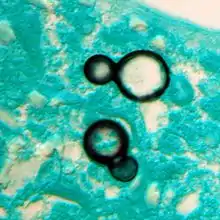

![]() | |

| Lung infiltration in blastomycosis. | |